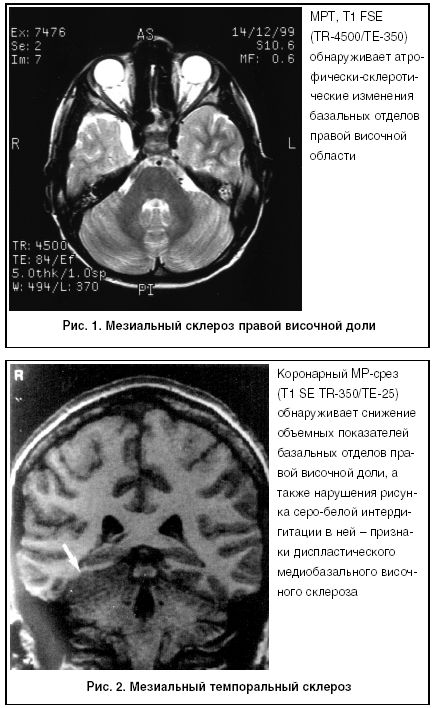

Особого внимания заслуживает визуальная характеристика повреждений, которые жестко сопряжены с эпилептическими приступами, как правило, резистентными, при которых возможности медикаментозной терапии крайне ограничены. К таким структурным изменениям в первую очередь относится мезиальный (гиппокампальный) склероз (рис. 1, 2). Он является мишенью наибольшего числа хирургических вмешательств, так как именно на нем лежит ответственность за развитие резистентной височной эпилепсии, как наиболее тяжелой формы, сопровождающейся нарушением интеллектуальных функций.